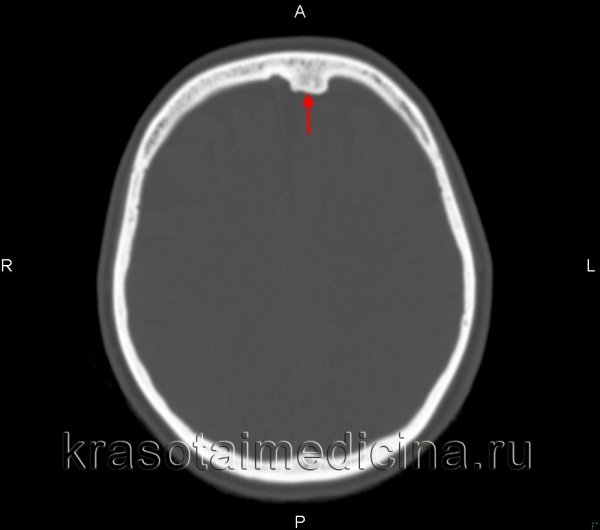

Основной способ диагностики – рентгенография. На снимке это будет выглядеть как однородная по структуре округлая опухоль с четкими границами. Остеоидная остеома на снимке представляет собой нечеткий дефект – очаг деструкции.

- Рентгенография позволяет узнать: месторасположение остеомы в кости, строение опухоли, степень деструкции кости, на которой находится новообразование, – а также определить, единичная опухоль или это множественное разрастание.

- Доброкачественность опухоли подтверждается медленным ростом, правильной структурой и геометрией, четким контуром, минимальным обызвествлением.

- При очень маленьких остеомах рентгенография не информативна, поэтому проводится компьютерная томография, позволяющая визуализировать малейшие детали структуры опухоли и замерить размеры деструкции.

б) Диагностика. При компьютерной томографии остеомы глазницы определяется объемное образование костной плотности на широком основании или на ножке, развивающееся из в остальном нормальной костной ткани, обычно лобной или решетчатой кости. Костный тип по строению идентичен костной ткани; фиброзный тип менее плотный и может напоминать фиброзную дисплазию.

Диагноз остеомы выставляется на основании дополнительных исследований. На начальном этапе выполняется рентгенография. Однако такое исследование не всегда эффективно из-за небольших размеров остеом и особенностей их расположения (например, на внутренней поверхности костей черепа). Поэтому основным методом диагностики часто становится более информативная компьютерная томография.

Диагноз остеоидной остеомы выставляется на основании характерной рентгенологической картины. Обычно из-за своего расположения такие опухоли лучше видны на рентгеновских снимках по сравнению с обычной остеомой. Однако в ряде случаев также возможны затруднения из-за малого размера остеоидной остеомы или ее локализации (например, в области позвонка). В таких ситуациях для уточнения диагноза используется компьютерная томография.

В ходе рентгенологического исследования под кортикальной пластинкой выявляется небольшой округлый участок просветления, окруженный зоной остеосклероза, ширина которой увеличивается по мере прогрессирования заболевания. На начальном этапе определяется четко видимая граница между ободком и центральной зоной остеомы. В последующем эта граница стирается, так как опухоль подвергается обызвествлению.